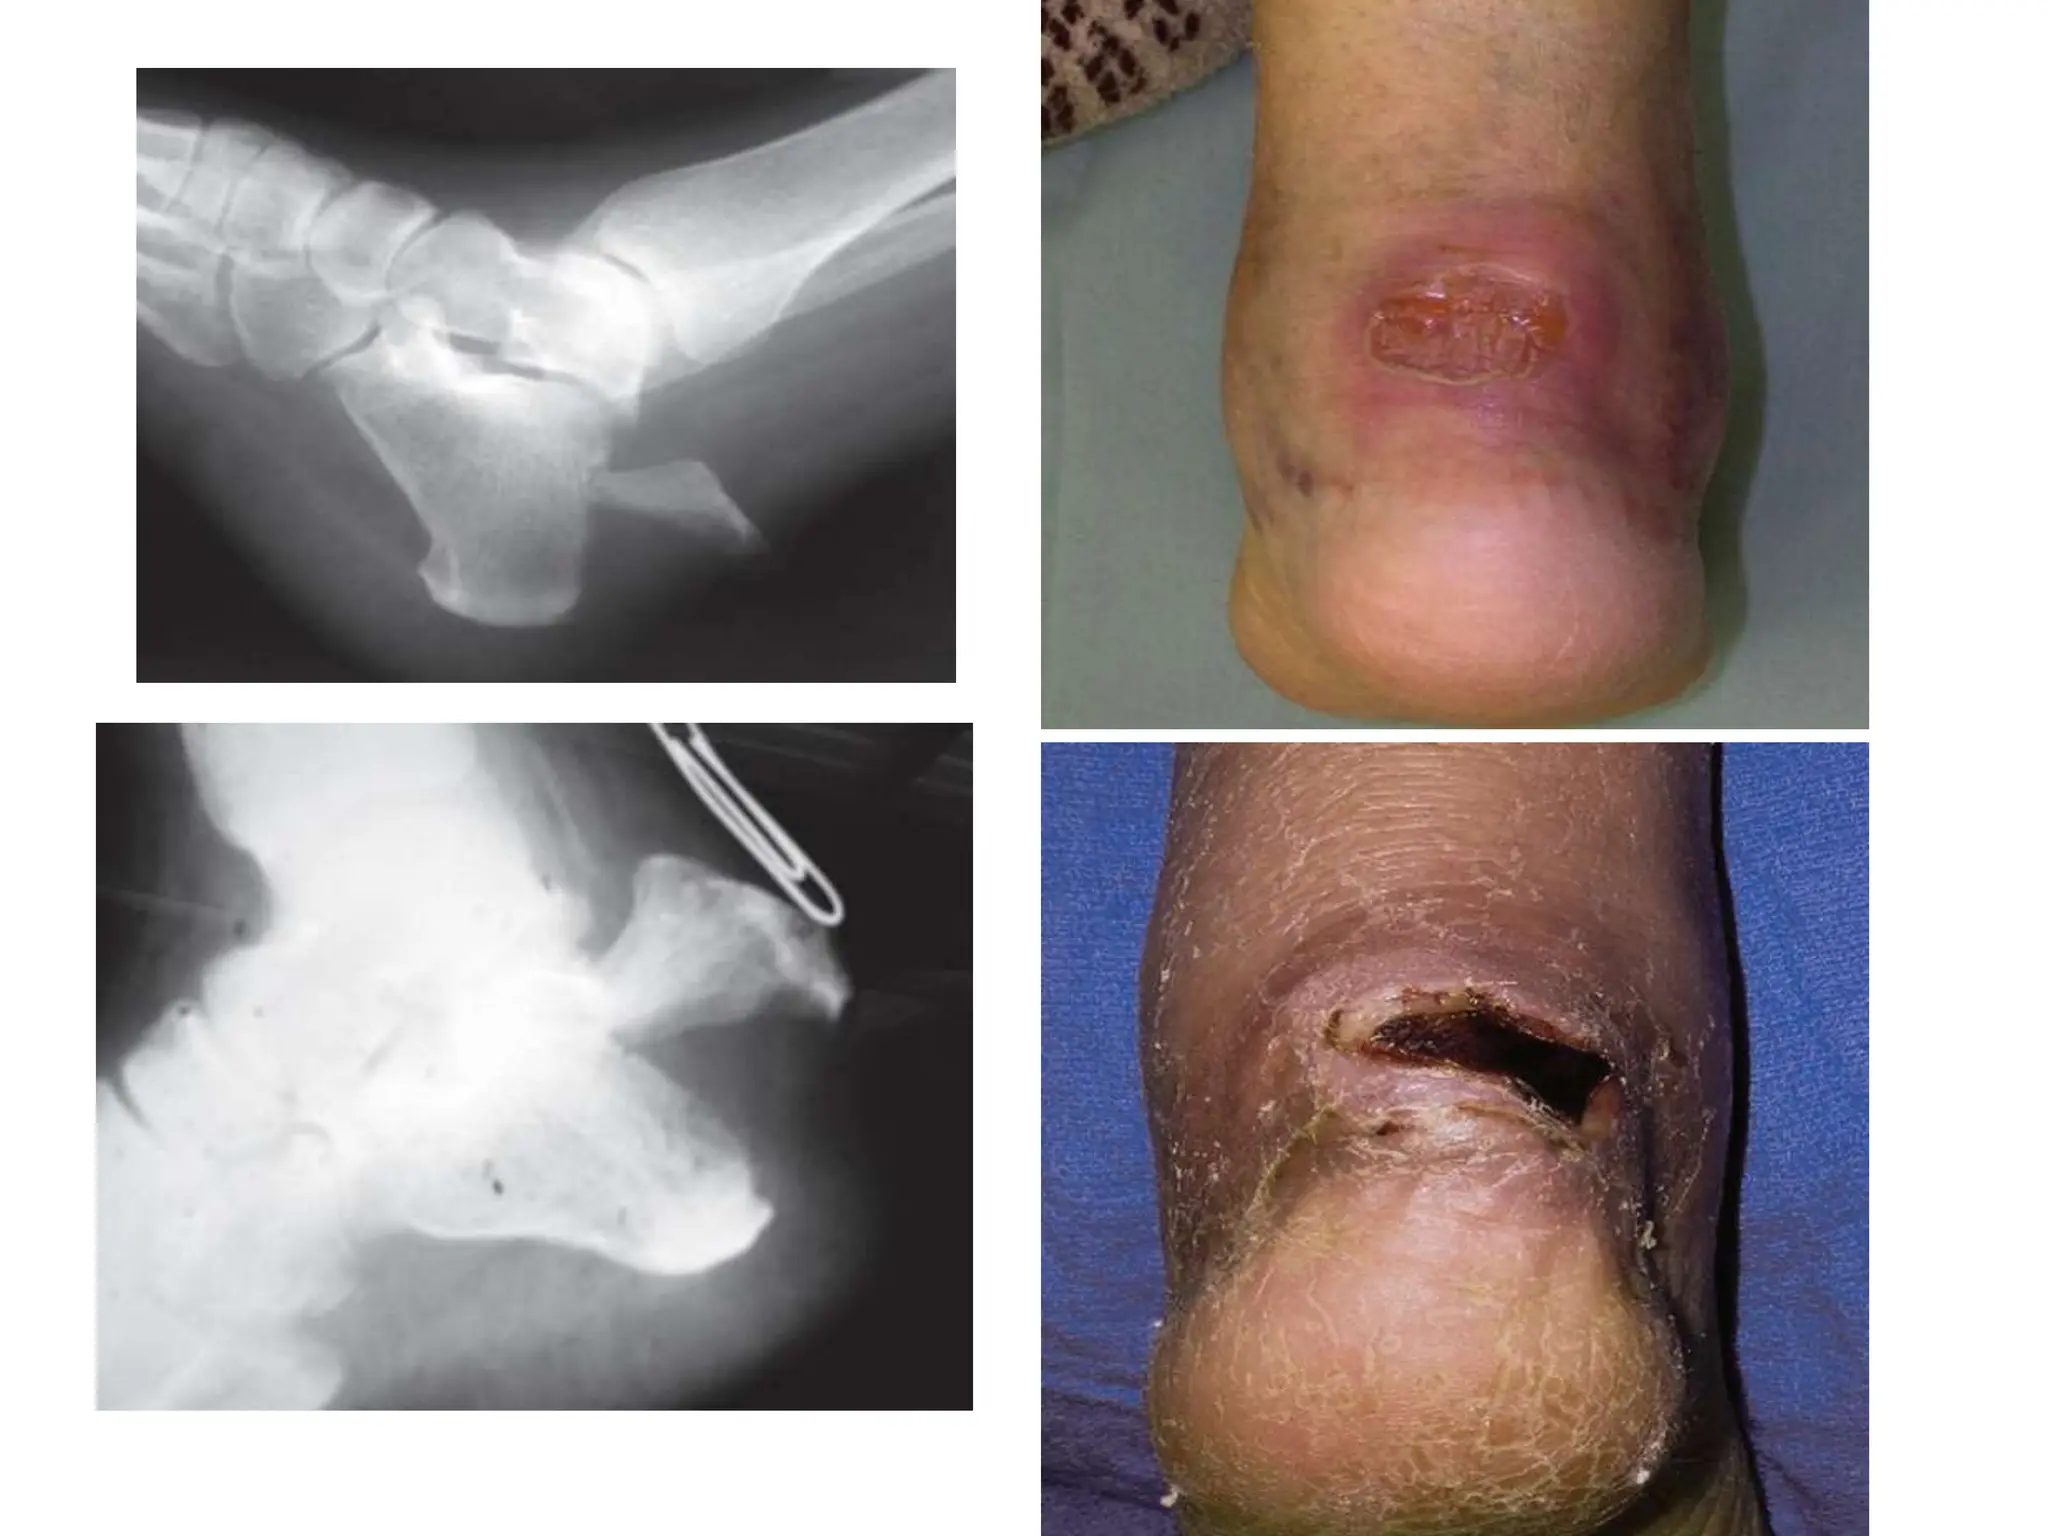

TUBEROSITY (AVULSION) FRACTURES

• The posterior skin is at risk from pressure from the

displaced tuberosity

• The posterior portion of the bone is extremely

prominent and will affect shoe Wear

• The gastrocnemius–soleus complex is

incompetent

• The avulsion fragment involves the articular

surface of the joint

1.Wound Necrosis

secondary infection

 exposure of the bone and fixation hardware

• Risk factors

peripheral vascular disease or

systemic disease such as diabetes mellitus

Cont’d….

Displaced fractures of the calcaneal tuberosity,

with or without skin compromise